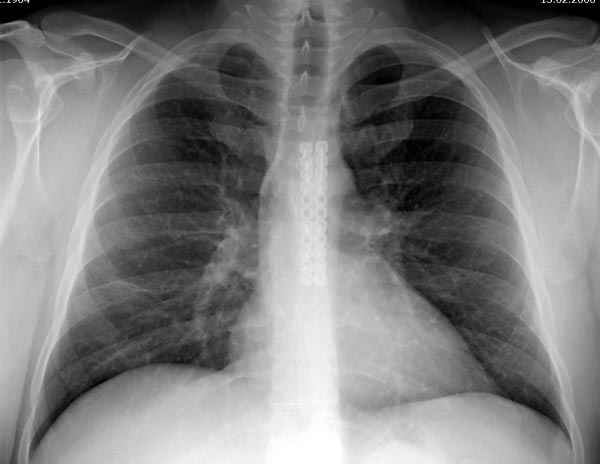

Глубокоуважаемые коллеги, Обратились за советом коллеги из соседней больницы. Мужчина 30 лет, в автоаварии ударился грудью об руль. После травмы 3 недели. Определяется отчетдивая подвижность на месте перелома. Снимок в приложении. Пока обсуждали варианты - LCP (какую?) или спицы. Открывать зону перелома или нет? Что посоветуете?

Пару лет назад коллега из грудной хирургии направил больного с хроническими жалобами на боли по поводу ложного сустава грудины.

Оперировали вместе с грудным хирургом и в нашем случае главной причиной была болезненность. Во время операции приняли все меры предосторожности недопущения прокола средостения (см. на 4 снимке близкий контур сердца!!)

Ложный сустав зафиксирован двумя пластинами 2.4 мм (locking plate) позаимствованными из челюстно-лицевой хирургии, с костной пластикой, все остальные пластины мне показались слишком толстыми, грубые для грудины или отсутсвовали возможности создания угловой стабильности.

Рентген снимки во время операции и последние сделаны на днях.